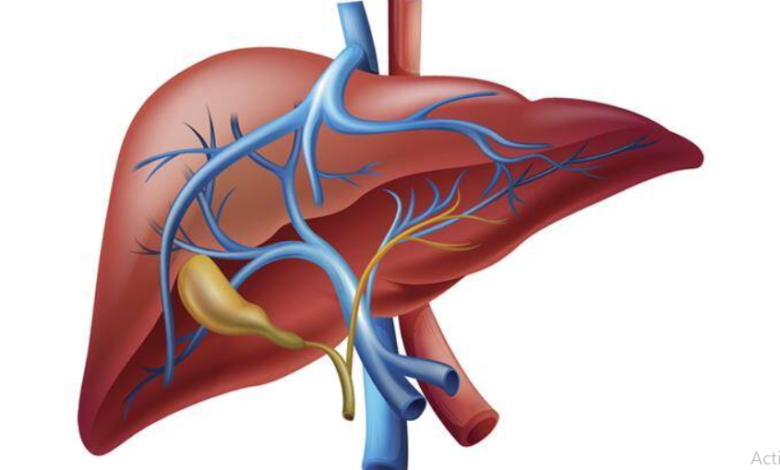

काठमाडाैँ : अस्वस्थ जीवनशैली र खानपानका कारण कलेजोमा क्षति पुगेका केही लक्षणहरू राती देखिने गर्छन् । यी लक्षणहरू समयमै पहिचान भएमा कलेजोलाई क्षति हुनबाट जोगाउन सकिन्छ।

अचेल बिग्रिएको जीवनशैली र अस्वस्थकर खानपानका कारण कलेजोमा क्षति पुगेको छ । यही कारणले गर्दा आजकल अधिकांश मानिसहरू कलेजोसँग सम्बन्धित कुनै न कुनै समस्याबाट त्रसित छन्। त्यसैले कलेजोको स्वास्थ्यमा विशेष ध्यान दिनु आवश्यक हुन्छ ।

कलेजोमा क्षति पुगेका केही लक्षणहरू राति देखिन्छन्। यी लक्षणहरू (लिभर डॅमेज साइन्स) समयमै पहिचान भएमा कलेजोलाई क्षतिबाट जोगाउन सकिन्छ। जान्नुहोस राति कलेजो बिग्रने लक्षण…

कलेजोसँग सम्बन्धित कुनै किसिमको समस्याका कारण छालामा चिलाउने समस्या आउन सक्छ। दिउँसो धेरै पटक चिलाउने कारण पत्ता लाग्दैन, तर रातमा यस्तो भयो भने सावधानी अपनाउनु पर्छ। किनकि राति चिलाउने, जलन हुने जस्ता लक्षणहरू कलेजोसँग सम्बन्धित समस्याको लक्षण हुनसक्छन्। त्यसैले यसलाई बेवास्ता गर्नुको सट्टा चिकित्सकको सल्लाह लिनुपर्छ ।

कलेजोसँग सम्बन्धित कुनै किसिमको समस्या भएमा वा कलेजो बिग्रन थाल्यो भने कमजोर हुन थाल्छ । राति, जब शरीरको धेरैजसो रगत कलेजोमा जम्मा हुन थाल्छ, त्यसको आकार बढ्न थाल्छ र दबाब बढ्न थाल्छ। यस्तो अवस्थामा कलेजोमा पीडा हुन थाल्छ । यो चिन्ताजनक हुन सक्छ।

कलेजोको क्षतिको सुरुमा खुट्टा र खुट्टा सुन्निन सक्छ। यदि यी लक्षणहरू राति देखा पर्छन् भने, सावधानी अपनाउनु पर्छ, किनभने रातमा कलेजोमा रगतको मात्रा बढ्छ र दबाबको कारण, कलेजो बढी प्रभावित हुन सक्छ।

यदि तपाईंको पिसाबको रंग परिवर्तन हुँदैछ भने यो कलेजोसँग सम्बन्धित रोगहरूको संकेत हुन सक्छ। वास्तवमा, कलेजोको क्षतिको कारण बिलिरुबिनको स्तर अचानक बढ्छ। जसका कारण मृगौलामा स्राव हुन थाल्छ । जसका कारण पिसाबको रंग परिवर्तन हुन्छ । यदि यो रातमा भयो भने यो अझ खतरनाक हुन सक्छ, किनभने रातमा कलेजोमा दबाब बढ्न सक्ने सम्भावना हुन सक्छ।

कलेजो सम्बन्धी कुनै पनि प्रकारको समस्या भएका मानिसहरूलाई अक्सर वाकवाकी लाग्ने जस्ता लक्षणहरू महसुस हुन्छन्। दिउँसो शारीरिक क्रियाकलाप नगर्दा पनि यस्ता समस्या आउन सक्छन् तर रातिमा यस्ता लक्षण देखिएमा सचेत हुनुपर्छ ।